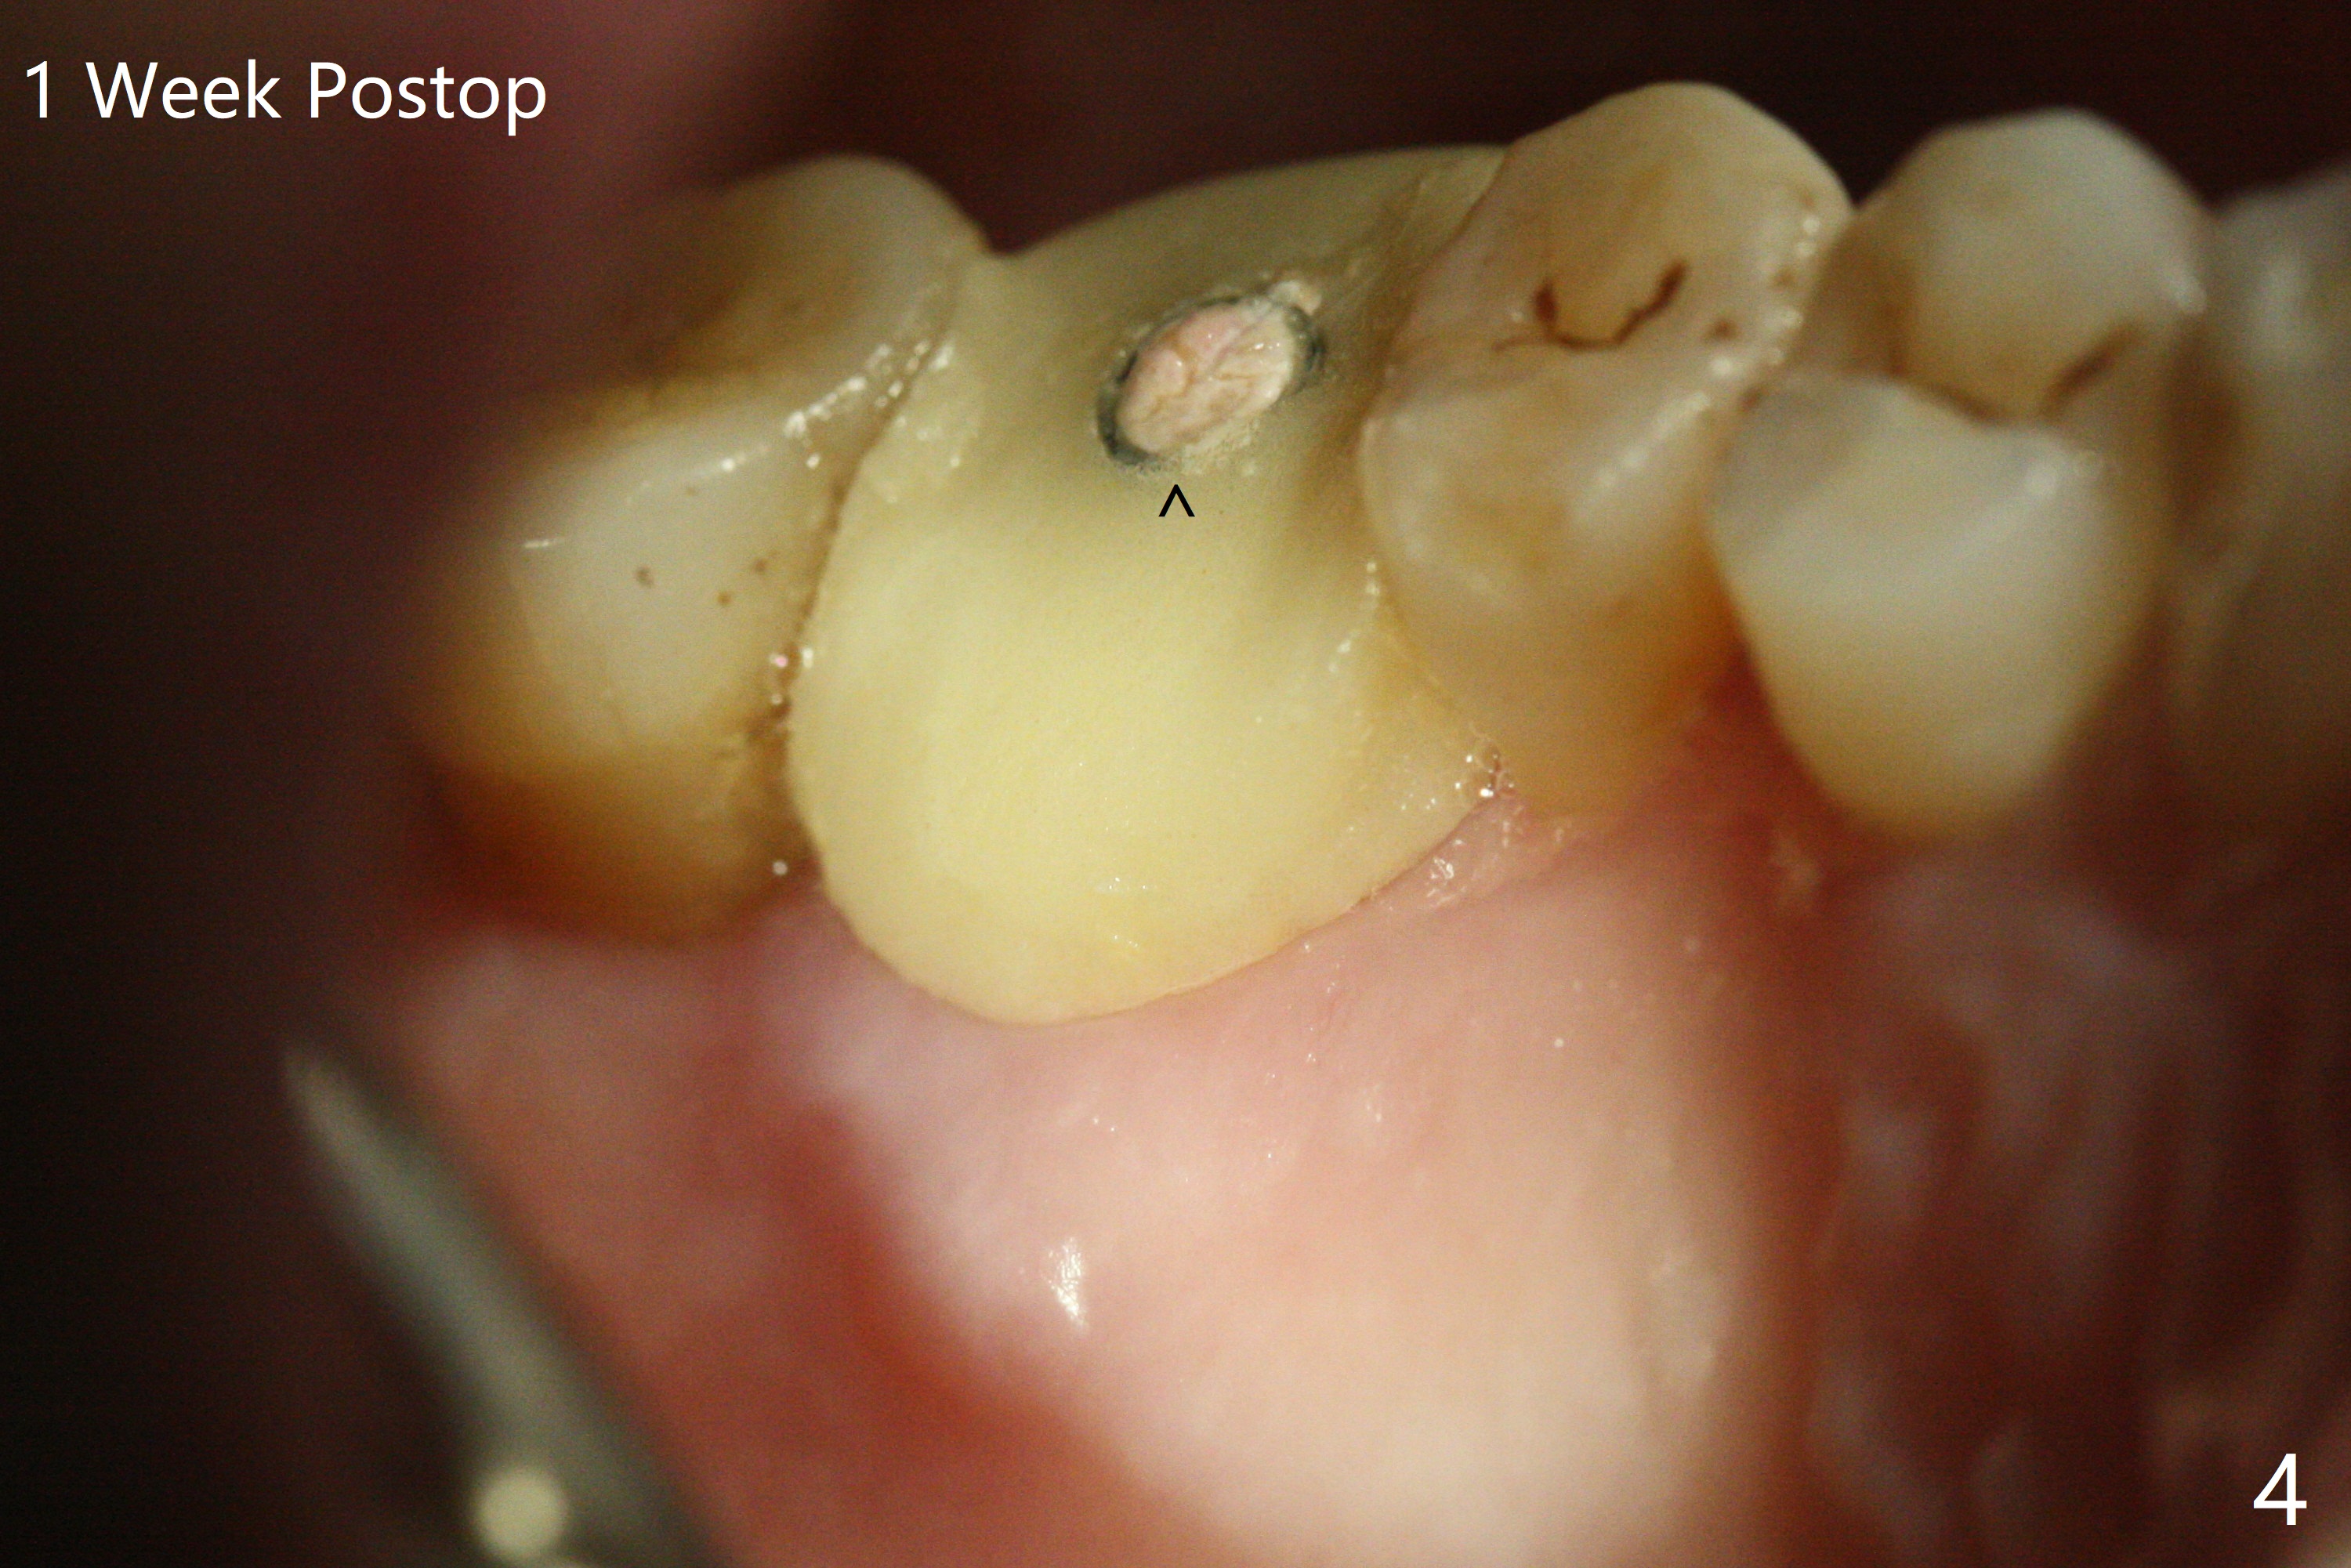

After extraction and debridement, osteotomy is initiated in the mesiobuccal socket free hand. Since the remaining bone is ~ 2 mm, the sinus floor is perforated suddenly. Fortunately the sinus membrane is not, as related to its thickening (similar to water ballooning, without symptom). Use 2-3.5 mm drills to enlarge the bony perforation (mainly lateral movement), followed by pushing bone graft upstairs with a curette (Fig.1 *); insert a 4x9 mm dummy implant (Fig.1) to determine the length of the final implant (Fig.2,3). A drawback of this case is the low torque (<20 Ncm), considering the thin bone. Following deeper implant placement, a 5.2x6(2) mm temporary abutment is placed for an immediate provisional to keep large amount of bone graft in place (Fig.3 *). There is no pain 1 week postop, while the immediate provisional remains stable partially because of the temporary abutment (Fig.4 ^). Four months postop, the temporary crown is loose. After removal of the temp and the temp abutment, gingival cuff is erythematous. A 6x4 mm healing abutment is placed. The bone graft (Fig.3 *) appears to have attached to the root of the neighboring tooth and the implant threads 7 months post op (COVID 19, Fig.5 arrowheads)). The bone graft appears to continue to merge with the neighboring root, bone and implant 10 months postop (2.5 months post cementation, Fig.6). The bone graft in the sinus seems to collapse and condense 10 months postop (Fig.7 *).